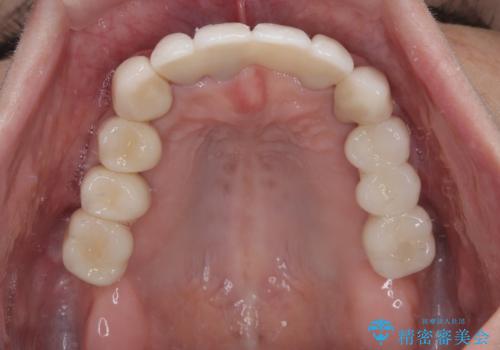

上顎口蓋からの堅い歯肉を移植する角化歯肉移植術を行いたかったのですが、体調不良から実施しなかったため、最終補綴物であるオールセラミッククラウンを装着した後に、知覚過敏や境目が見てしまうといった問題が一部で発生いたしました。

最終的には痛みや違和感のない状態にて治療を終えることができました。